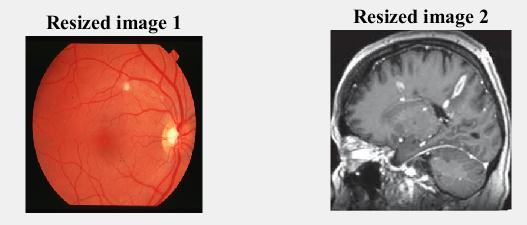

Watermarking when using Brain MRI and Retina images

Fig -5(a):Inputimagesforwatermarking

The cover image is at the left, at the same time as the watermarkimageisattheright,asshowninfig.5(a).When we apply the watermark embedding to the MRI of brain database all the images arehidden under cover image but earlierthanmakinguseofthewatermarkthepre-processing levelisinvolved.

Fig -5(b):inputimagesafterpreprocessing

Asillustratedinfig5(b),theinputimagesarerescaledtoa consistentsize.